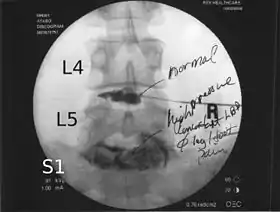

![]() Lumbar provocative discography showing a degenerated disc, L5-S1 with normal disc L4-L5 | |